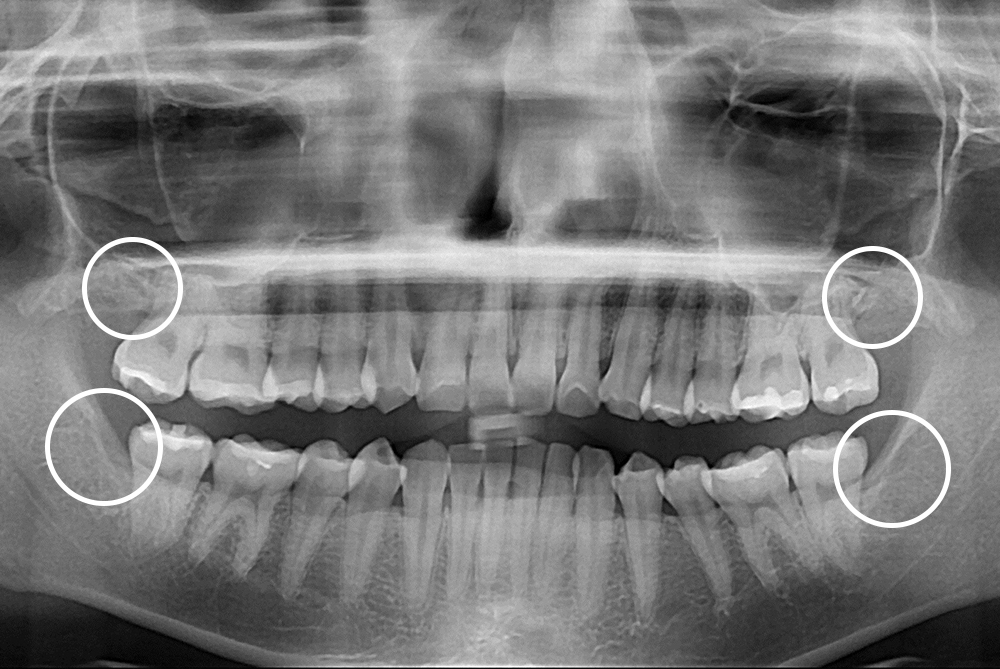

[사랑니] 매복 사랑니 발치

치료후 : 2021-04-24

세종치과는 구강악안면외과학 박사이신 원장님이 발치하는 치과입니다.